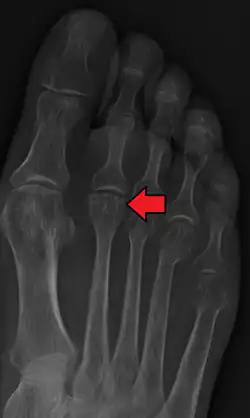

Accurate diagnosis of Freiberg disease typically involves a combination of clinical examination and imaging studies:

- Radiography: X-rays may reveal flattening, sclerosis, or fragmentation of the metatarsal head.